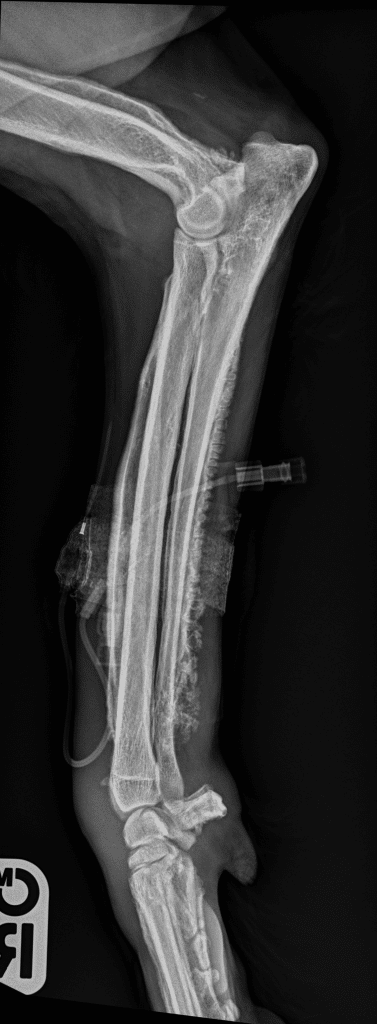

What Sybil actually had was hypertrophic osteopathy. This is a very rare condition which results in a type of bone overgrowth. Hypertrophic osteopathy results in the development of pathognomonic palisading new bone oriented perpendicular to the long axis of long bones, involving the diaphysis and metaphyses. This results in the overlying soft tissue swelling. It often occurs secondary to distant disease in the chest cavity. Therefore we did further investigations of her chest and did indeed find a small tumour.